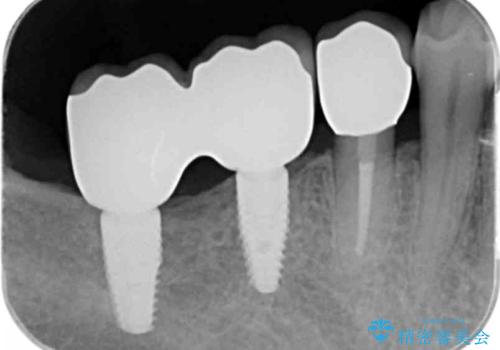

奥歯 インプラントによる機能回復

- 45万円(ストローマンインプラント・骨造成・チタンカスタムアバットメント・ジルコニアクラウン)費用は治療当時の料金となります

奥歯のインプラント治療について

最後方臼歯はインプラントを用いることでしっかりと咬合機能を回復することができます。